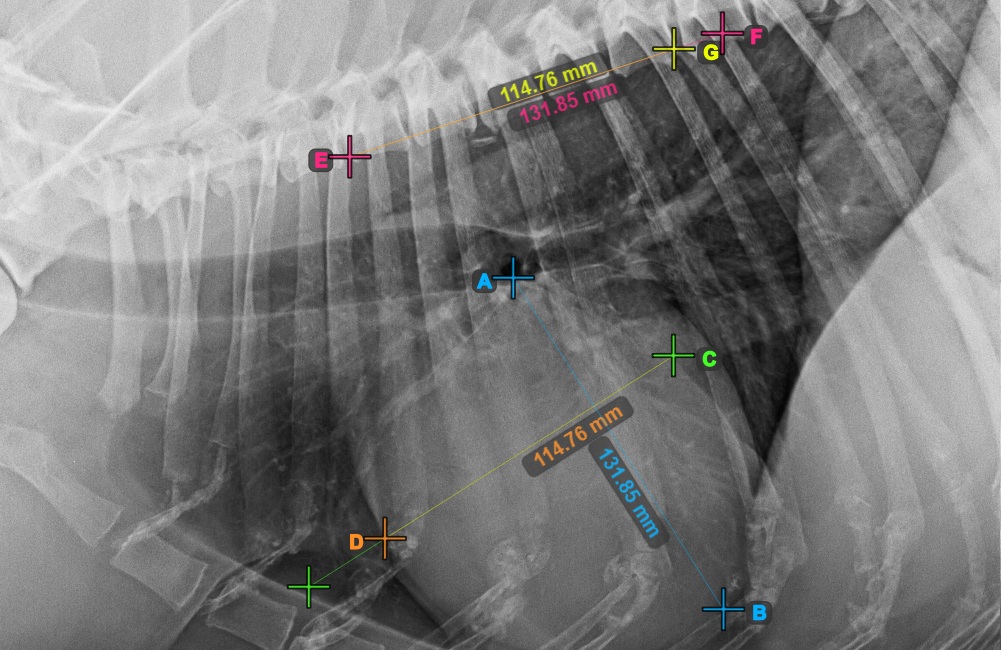

Identify the beginning of the T4 vertebra (the fourth vertebral body of the spine), counting from the initial point of the spine. Mark the beginning of the T4 vertebrae to continue the measurement. The software will draw lines from the marked point along the spine. The length of the lines depends on the measured long and short axes of the heart.

The image below represents the typical placement of the point at the beginning of the fourth vertebral body of the spine.

../../_images/image397.jpg

Before proceeding with the required VHS calculations, make sure that the lines are placed precisely along the vertebrae.

../../_images/image398.jpg